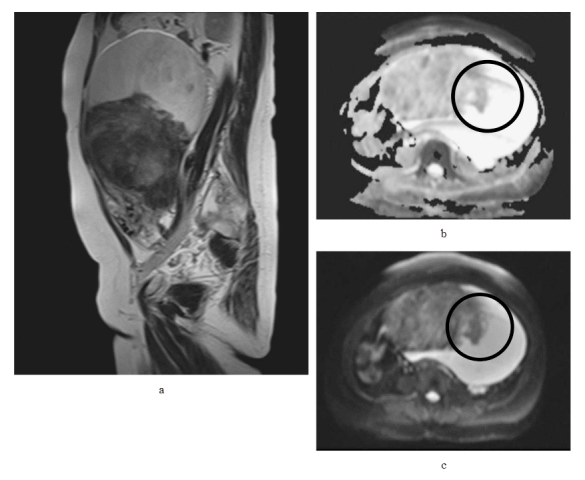

Uterine leiomyomas, benign tumors common in reproductive-aged women, can display rare variants such as hydropic leiomyoma (HL), which exhibit unique histological features like zonal edema and increased vascularity. However, due to its rarity, comprehensive clinical knowledge about HL is limited. We report a case of a 49-year-old Japanese woman who was premenopausal and nulliparous, presenting with a two-year history of abdominal distension. An MRI scan revealed a 20 cm mass in the posterior part of the uterus, exhibiting characteristics suggestive of an ovarian tumor. During laparotomy, a cystic tumor connected with a swollen fibroid was found, and pathology confirmed HL. This case emphasizes that hydropic leiomyomas can mimic malignant tumors on ultrasonography due to their atypical features, necessitating additional evaluations using alternative imaging techniques or histopathological examinations for accurate diagnosis and appropriate management. The patient recovered uneventfully, broadening our understanding of HL's clinical presentation.